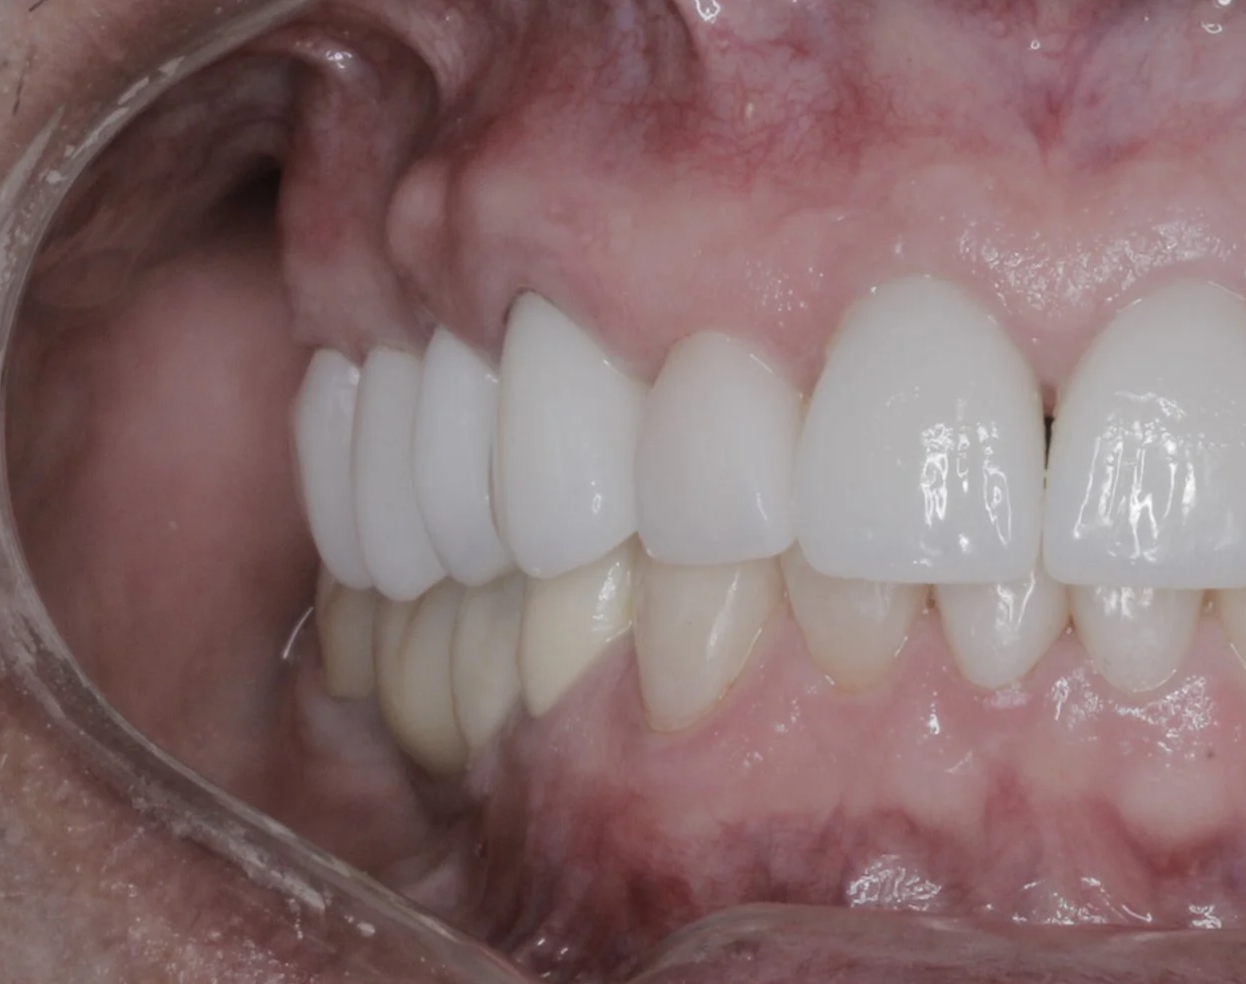

Después

Reemplazo de puente fijo + coronas

Nuevas coronas y carillas libres de metal de todos los dientes superiores.

Resultado final